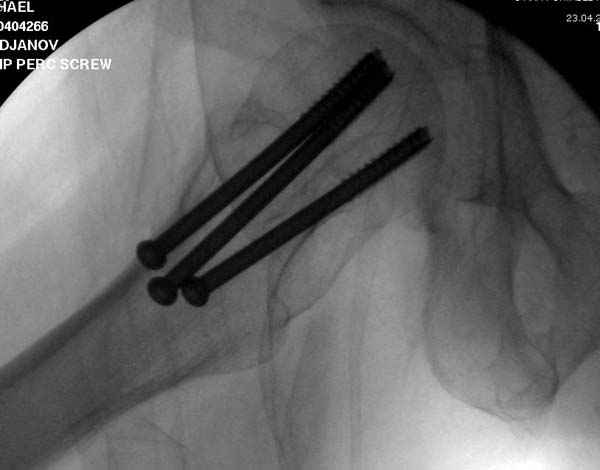

Профилактику дальнейшего раскола неполного перелома шейки провели тремя канюлированными шурупами.

На второй день после выписки упал дома. Снимки приложены. Коллеги рекомендуют удаление шурупа и вытяжение. Что делать?